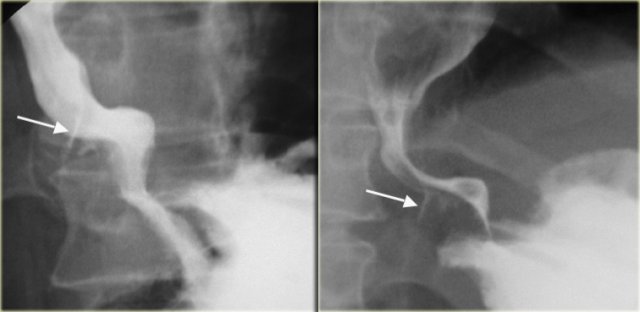

On the left a patient with a Mallory-Weiss tear.

Spot films show barium (arrows) in linear mucosal tear near gastroesophageal junction.

Tears may be in distal esophagus, gastric fundus, or extend across the GE junction.

On the far left an intramural extravasation (arrow) after distal dilation for achalasia.

In the middle an intramural extravasation (arrow) after complicated endoscopy.

On the right a perforation after biopsy with extravasation of contrast material (arrow).